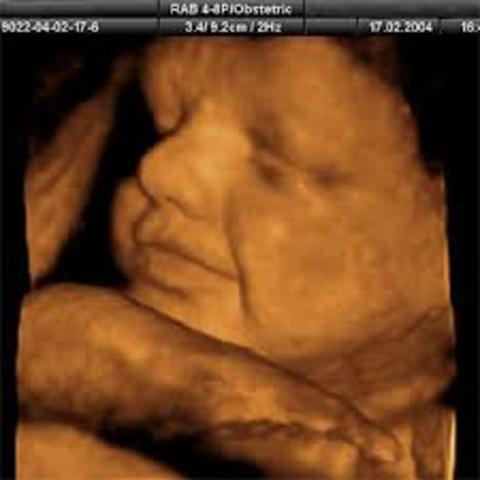

Los riñones de tu bebé producen orina y sus pulmones comienzan a respirar, su cerebro continúa creciendo y las uñas ya llegan a la punta de sus dedos, por lo que deberás cortárselas al poco tiempo de nacer. Su rostro también es más expresivo y a veces sacará la leng